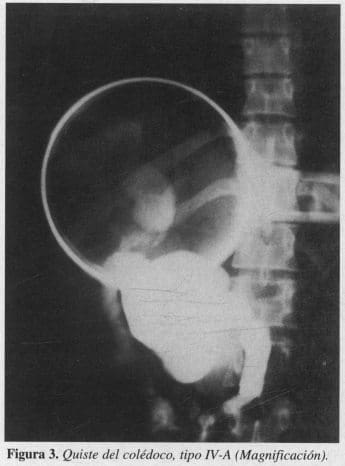

En 1958 Alonzo Lej presentó un artículo que compilaba 94 casos los cuales fueron clasificados morfológicamente en los tres grupos clásicos (8); en 1977 Todani y colaboradores presentaron la clasificación actualmente utilizada, siendo parcialmente modificada en 1990 por Manning y luego por Serena Serradel en 1991. Los quistes Tipo I o dilatación fusiforme del colédoco representan 85 a 90 % de todos los casos; son los predominantes en los niños y, en general, en todas las edades (5, 9). Los Tipo II o de forma diverticular conforman menos del 2% de los casos. Los Tipo III o coledococele, además de ser una forma infrecuente (2%), tienen la característica de ser intraduodenales o intrapancreáticos, y se subdividen en dos variantes de acuerdo con su origen: variante A si compromete la confluencia del colédoco y el Wirsung; y variante B si se originan a partir de la ampolla de Vater (1). Los Tipo IV representan una variedad multiquística que corresponde al 10% de los casos y puede ser subdividida en variante A, con compromiso intra y extrahepática, y variante B, confinada a la vía biliar extrahepática. Tipo V o síndrome de Caroli (11), y Tipo VI que es la dilatación quística del conducto cístico (Figura 1).

El análisis de los estudios imaginológicos fueron divididos en preoperatorios, intraoperatorios y postoperatorios. La ecografía se realizó en el 100 % de los pacientes y tuvo una especificidad de 88% en los estudios preoperatorios; otros métodos utilizados en este grupo de estudios preoperatorios fueron, tomografía axial computadorizada (TAC), colangiografía retrógrada endoscópica (CPRE) y gamagrafia. Intraoperatoriamente se utilizó en todos los pacientes la colangiografia intraoperatoria transvesicular, habiendo encontrado quistes del Tipo I en 90 % de los casos (9 pacientes), y 1 quiste Tipo IV variante A, en el 10 % restante (1 paciente) (Figuras 2 y 3). En el postoperatorio se realizó ecografía trimestral en el 100 % de los casos (10 pacientes); 1 paciente requirió colangiografía transparietohepática por sospecha ecográfica de estenosis, la cual fue confirmada mediante dicho examen.